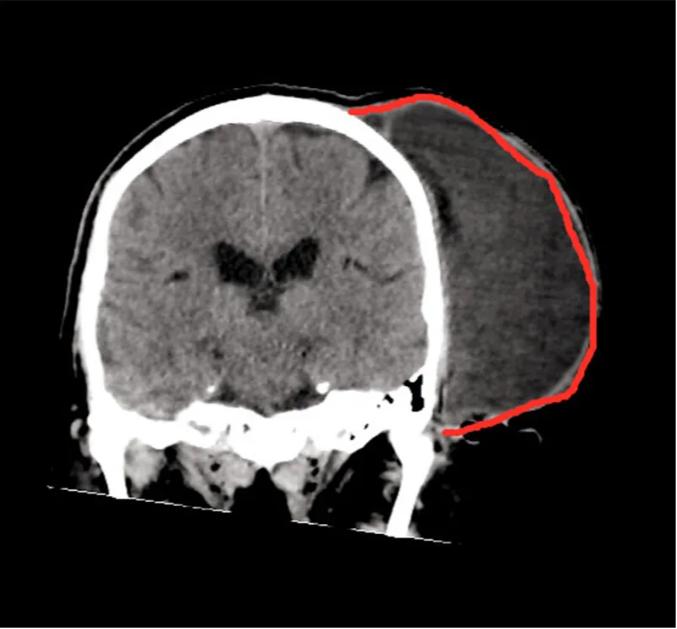

这个时候,邹先生才觉得事情没有那么简单,于是赶忙而自己带着去了湖南某家医院,这不查还好,一查CT竟显示是个“瘤”。

邹先生CT片

湖南省人民医院神经外科黄萌异主任表示, 邹先生头上的疙瘩是 皮脂腺瘤, 属于临床常见的良性皮肤病变,是因为头部的 毛囊代谢物长期无法排出所导致。 如果没有及时处理,肿块就会随着时间的推移,越来越大。